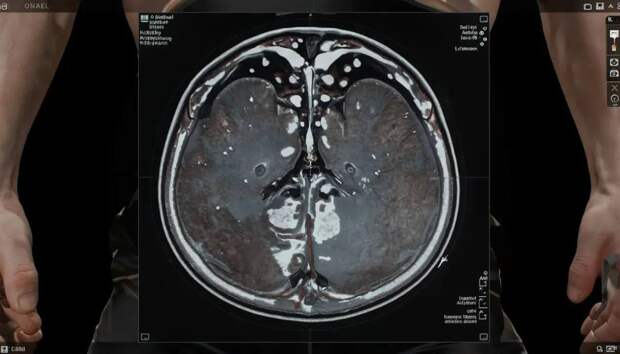

Для исследования мошонки и лимфатических узлов используют высокопольные МР-аппараты (обычно 1,5 Тесла и выше). В качестве контрастного вещества применяется гадолиний, который помогает выявить патологически изменённые узлы и опухоли.

Обследование включает получение сагиттальных, корональных и аксиальных изображений в различных режимах (T1, T2, с подконтрастным усилением). Такой подход позволяет оценить размеры, структуру и контрастную активность лимфатических узлов и тканей мошонки.